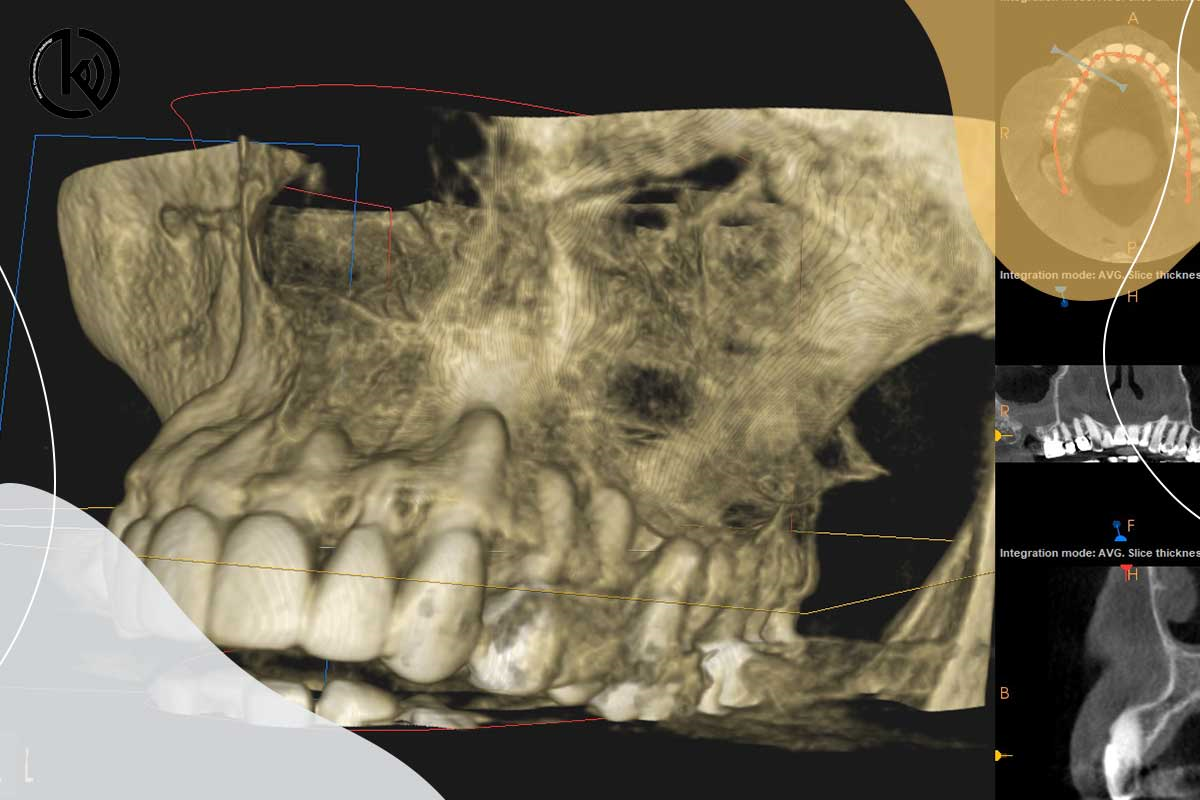

اسکن سه بعدی یا سی تی اسکن فک و دندان

هنگامی که دندانپزشک شما درمان ایمپلنت دندانی را برایتان درنظر گرفته باشد ، برای بررسی ابعاد استخوانی و آناتومی ناحیه مور...

بازسازی سه بعدی

با توسعه فناوری، استفاده از روش‌های تصویربرداری سه بعدی در دندانپزشکی برای تشخیص و بازسازی سه بعدی فک و صورت گسترش یافته...